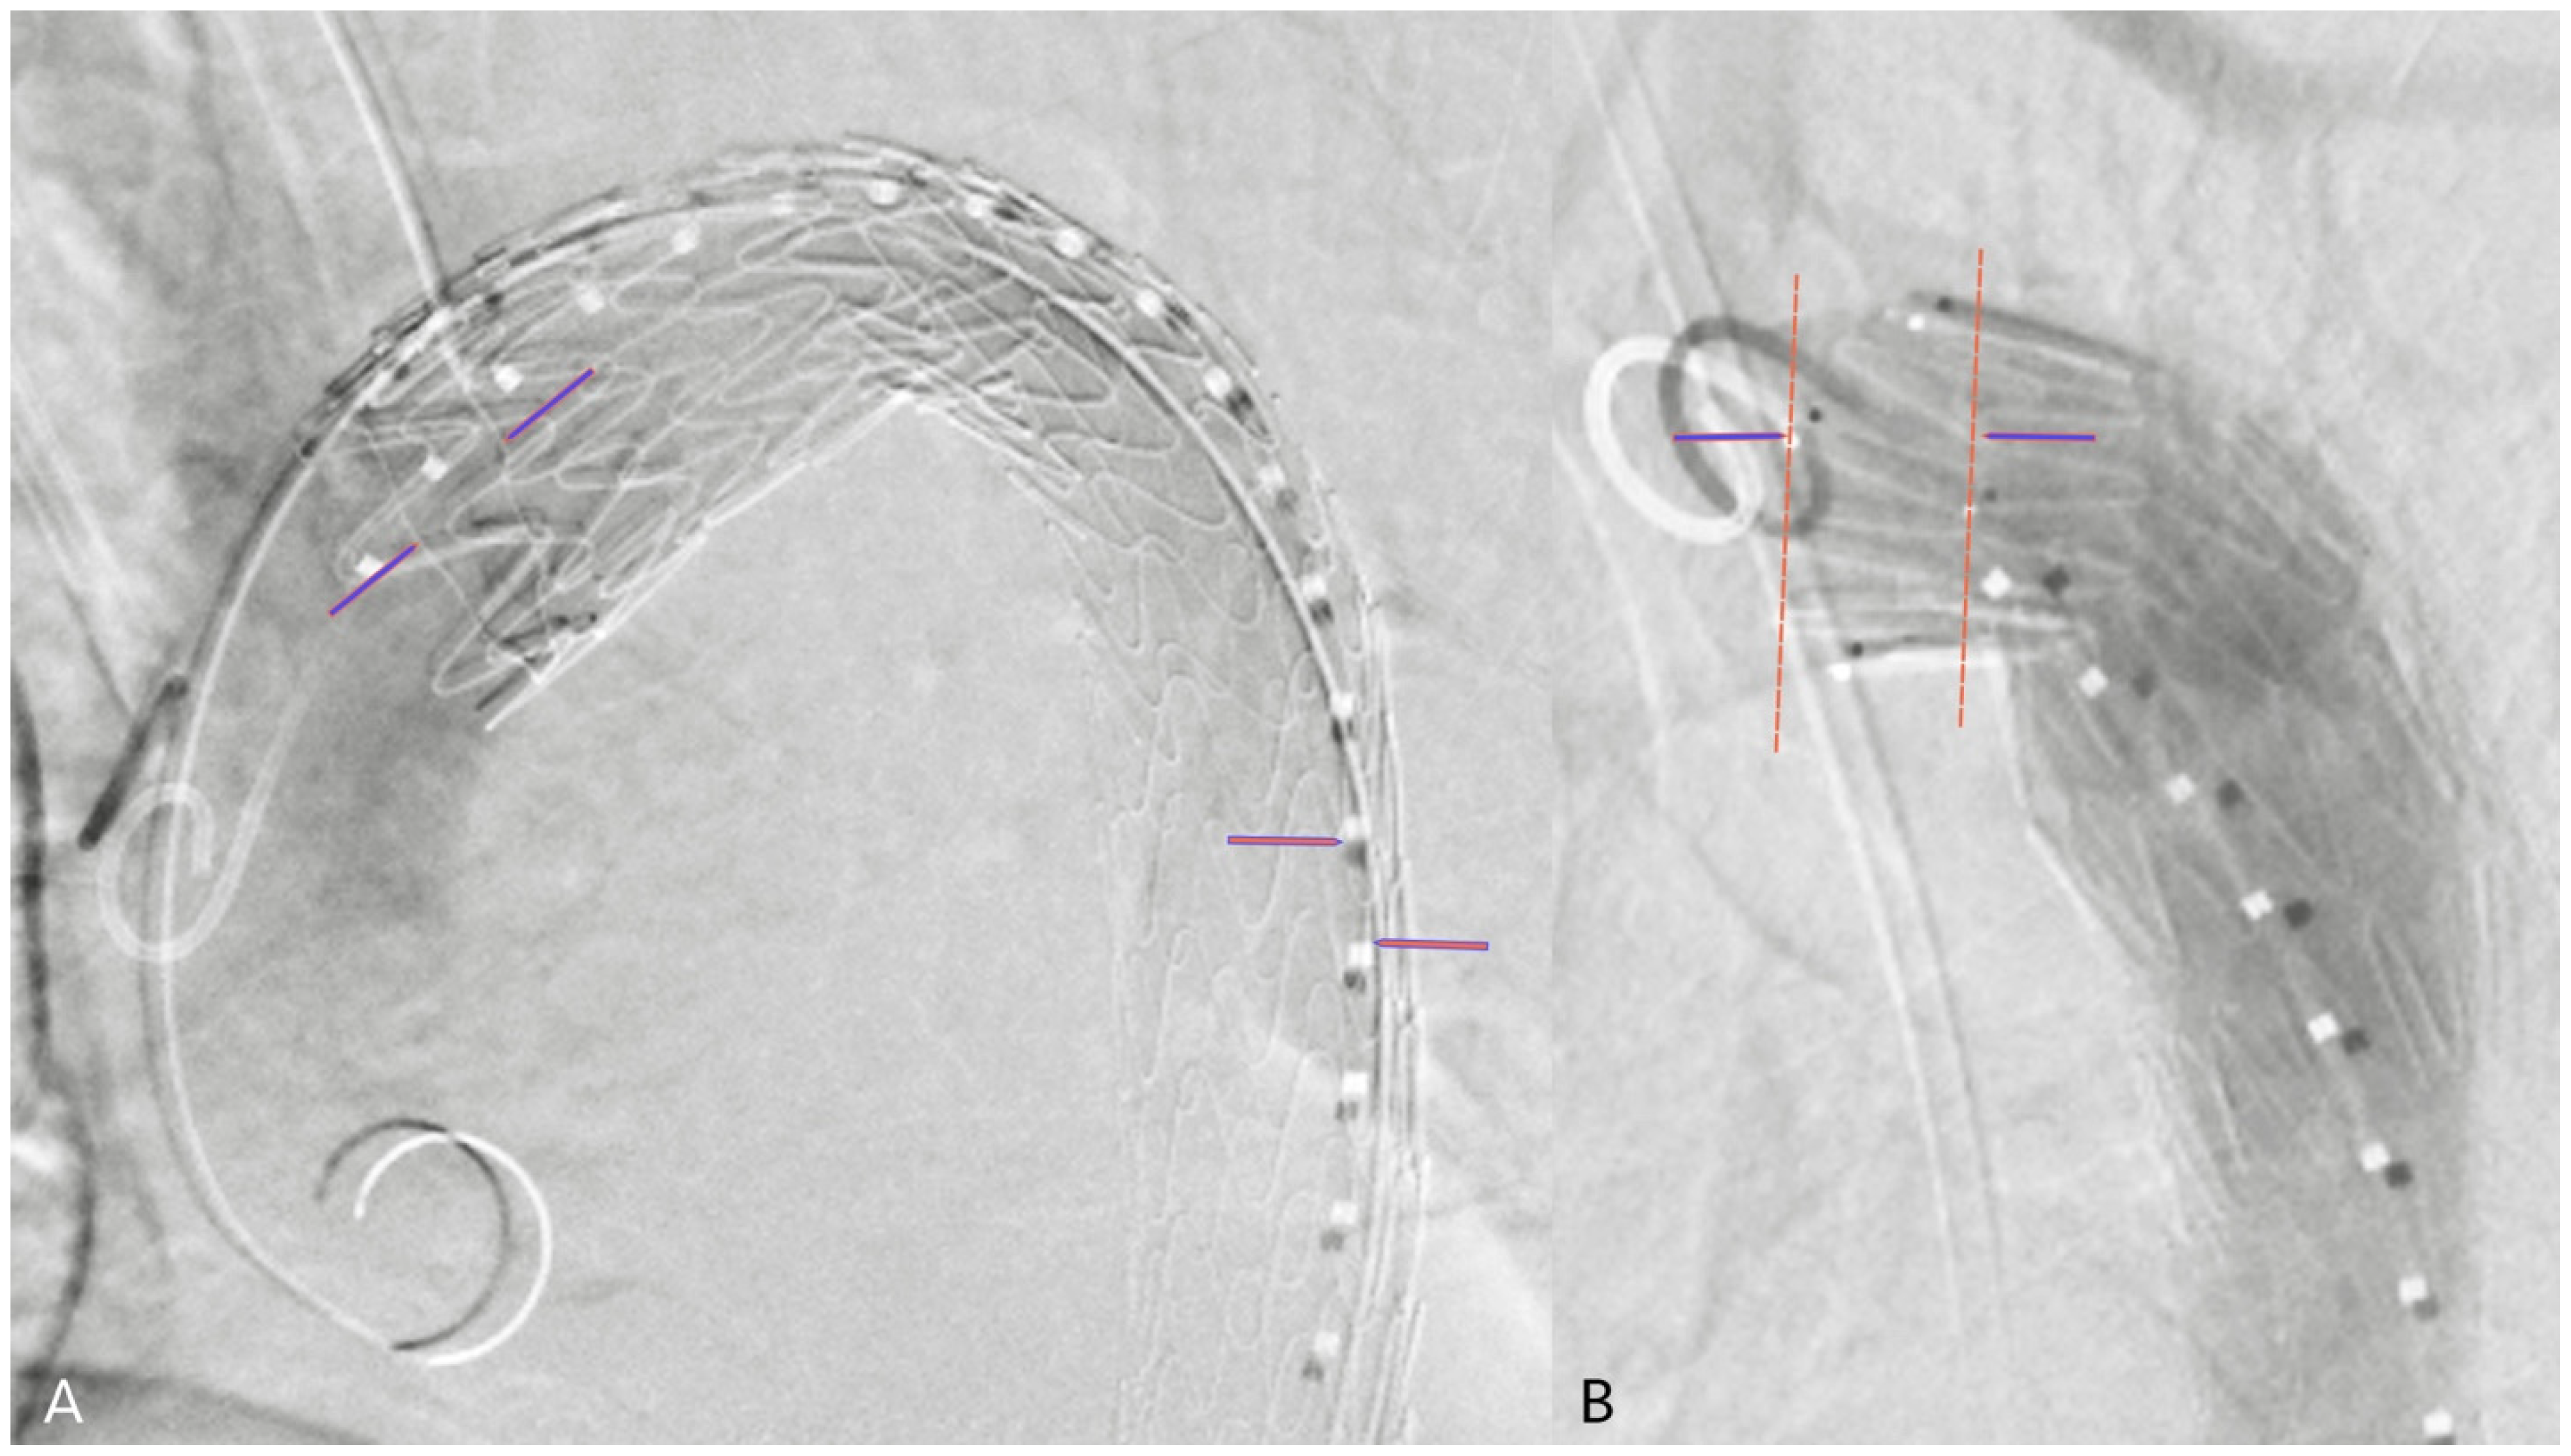

2.4. 2D3D Fusion Technique

2.5. 3D3D Fusion Technique